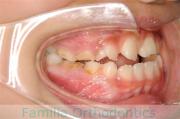

No.16V-139

- 叢生

- 16歳

- 男性

下の前歯が後ろにあるのが気になるとのことで来院されました。非抜歯で行うことも可能でしたが、上下左右から小臼歯抜歯をして治療を行うことをご希望になりました。

マルチブラケット法にて治療を行い、約3年、40回の通院が要でした。

かみ合わせが深い(上の前歯で下の前歯が覆われてしまう)ので、保定をしっかりしないと、また深くなってきてしまいやすいです。